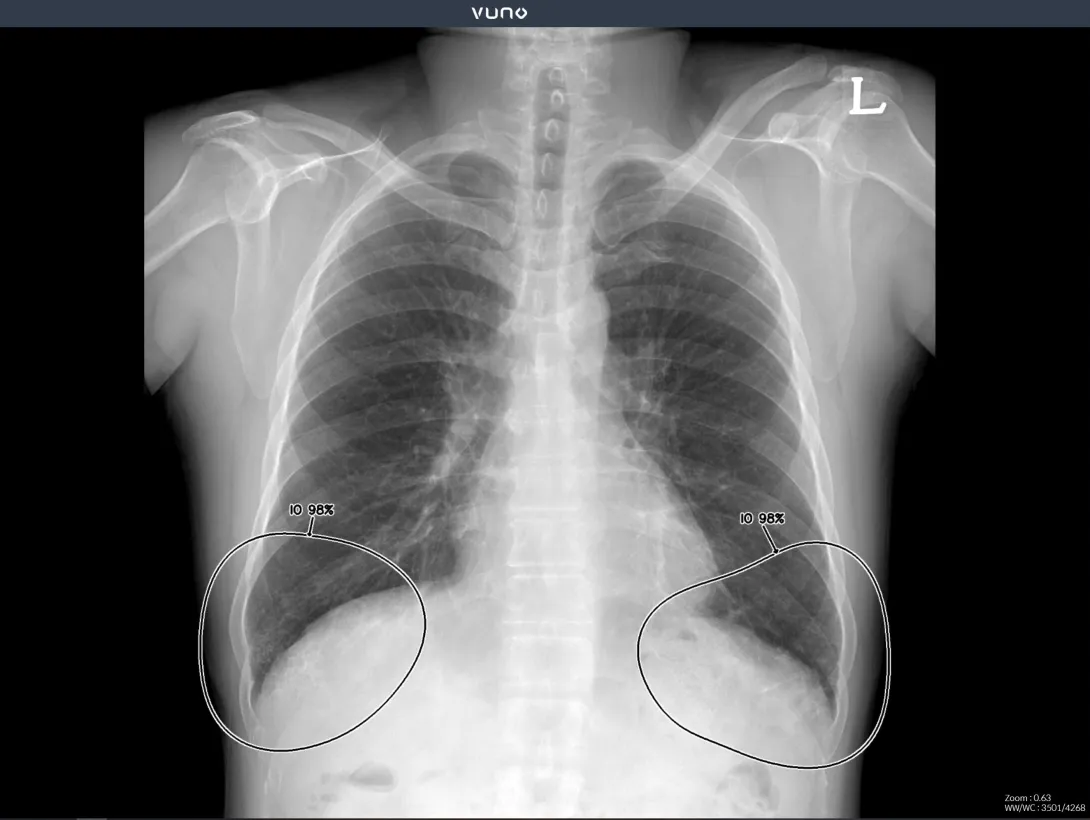

South Korean medical imaging firm VUNO has published a study showing that its Med-Chest X-Ray helps improves detection and localisation of major abnormal findings on chest radiographs, while reducing reading time. The study was published in the academic journal Radiology.

The study was conducted on three groups of people, each comprising assessors with varying experience levels – residents, board-certified radiologists, and thoracic radiologists. It compared the readings of chest radiographs from those who used the Med-Chest X-Ray against the readings of those who did not use the software.

It was shown that diagnostic accuracy across all performance, including per-lesion and per-image sensitivity, improved significantly. Reading time was also cut by an average of 50%.